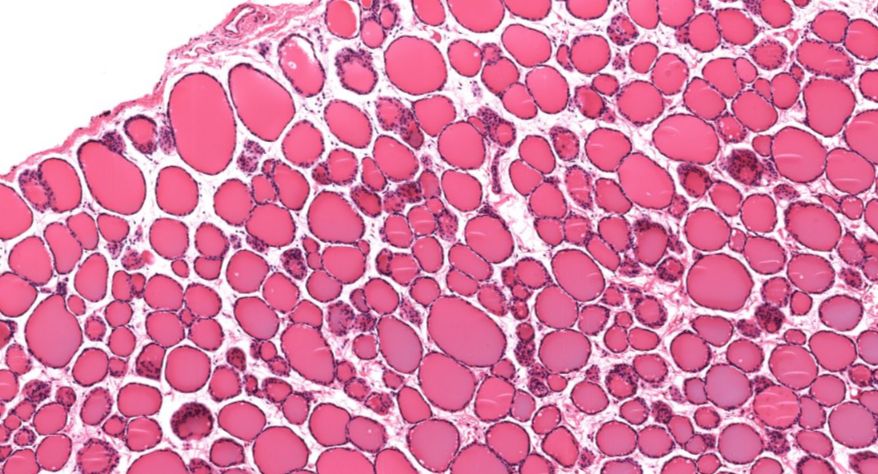

低倍镜观察:1. 被膜:由薄层结缔组织组成。2. 实质:由许多大小不等的滤泡构成。滤泡壁是单层立方上皮细胞,滤泡腔内充满粉红色匀质胶状物,滤泡之间的结缔组织内有丰富的血管。高倍镜观察:1. 滤泡:滤泡壁的单层滤泡上皮细胞一般呈低柱状或立方状,胞质着浅色,细胞核呈圆形。滤泡腔内充满了粉红色匀质胶质。2. 滤泡旁细胞:体积较大,呈圆形或椭圆形;细胞核较大,呈圆形,着色较浅,细胞质染色也较浅。细胞或嵌在滤泡壁上或成团分布于滤泡之间。3. 间质:由结缔组织组成。位于滤泡之间。其中含有丰富的毛细血管及三五成群的滤泡旁细胞。

2.滤泡